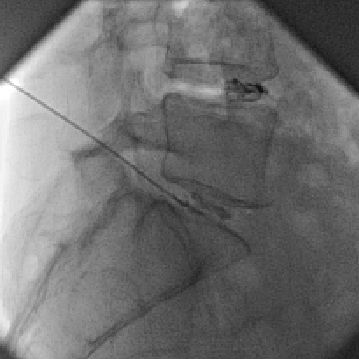

Μια τέτοια καινούρια για την Ελλάδα, θεραπευτική τεχνική, είναι η ενδοδισκική θεραπεία με DISCOGEL η οποία προσφέρει γρήγορη ανακούφιση από τον πόνο. Το DISCOGEL είναι μια φαρμακευτική ουσία η οποία αποτελείται από ζελατινοποιημένη αιθανόλη, αναμιγμένη με σκιαγραφική ουσία. Το φάρμακο χορηγείται εντός του πάσχοντος μεσοσπονδύλιου δίσκου, δια μέσω λεπτής βελόνας η οποία κατευθύνεται στον πυρήνα (κέντρο) του δίσκου, διαδερμικά, χωρίς τομή, υπο τοπική αναισθησία και ακτινοσκοπική καθοδήγηση.